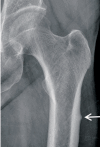

Nonsurgical Treatment Strategies after Osteoporotic Hip Fractures

Osteoporosis is a metabolic disease that is increasing in prevalence as people live longer. Because the orthopedic surgeon is frequently the first and often the only physician to manage patients with osteoporotic hip fractures, every effort should be made to prevent future fractures. A multidisciplinary approach is essential in treatment of osteoporotic fractures. Basic treatment includes calcium and vitamin D supplementation, fall prevention, hip protection, and balance and exercise programs. Currently available pharmacologic agents are divided into antiresorptive and anabolic groups. Antiresorptive agents such as bisphosphonates limit bone resorption through inhibition of osteoclastic activity. Anabolic agents such as parathyroid hormone promote bone formation.